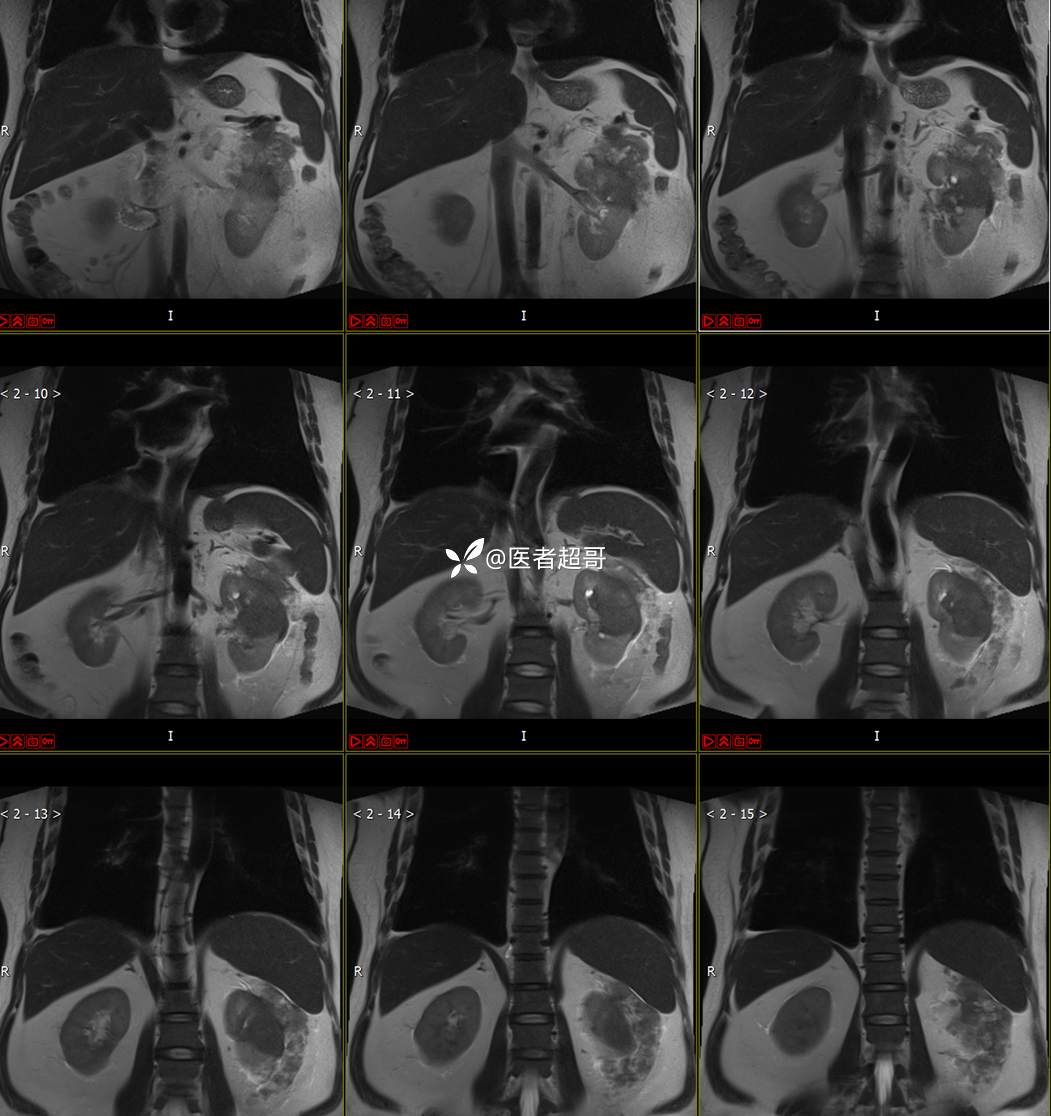

主 诉:查体发现左肾肿物9天。

现病史:患者9天前于附属医院行常规腹部CT检查时,发现左肾占位性病变并肾周脂间隙软组织增多,自述无明显腰腹部不适,无尿频、尿急、尿痛及肉眼血尿,未予特殊治疗,患者近期无头晕头迷,胸闷气急,腹胀腹泻及其他部位明显不适,遂至我院就诊,门诊以“肾肿物”收入院,患者自发病以来,精神可,睡眠饮食可,大便正常,体重无明显减轻。